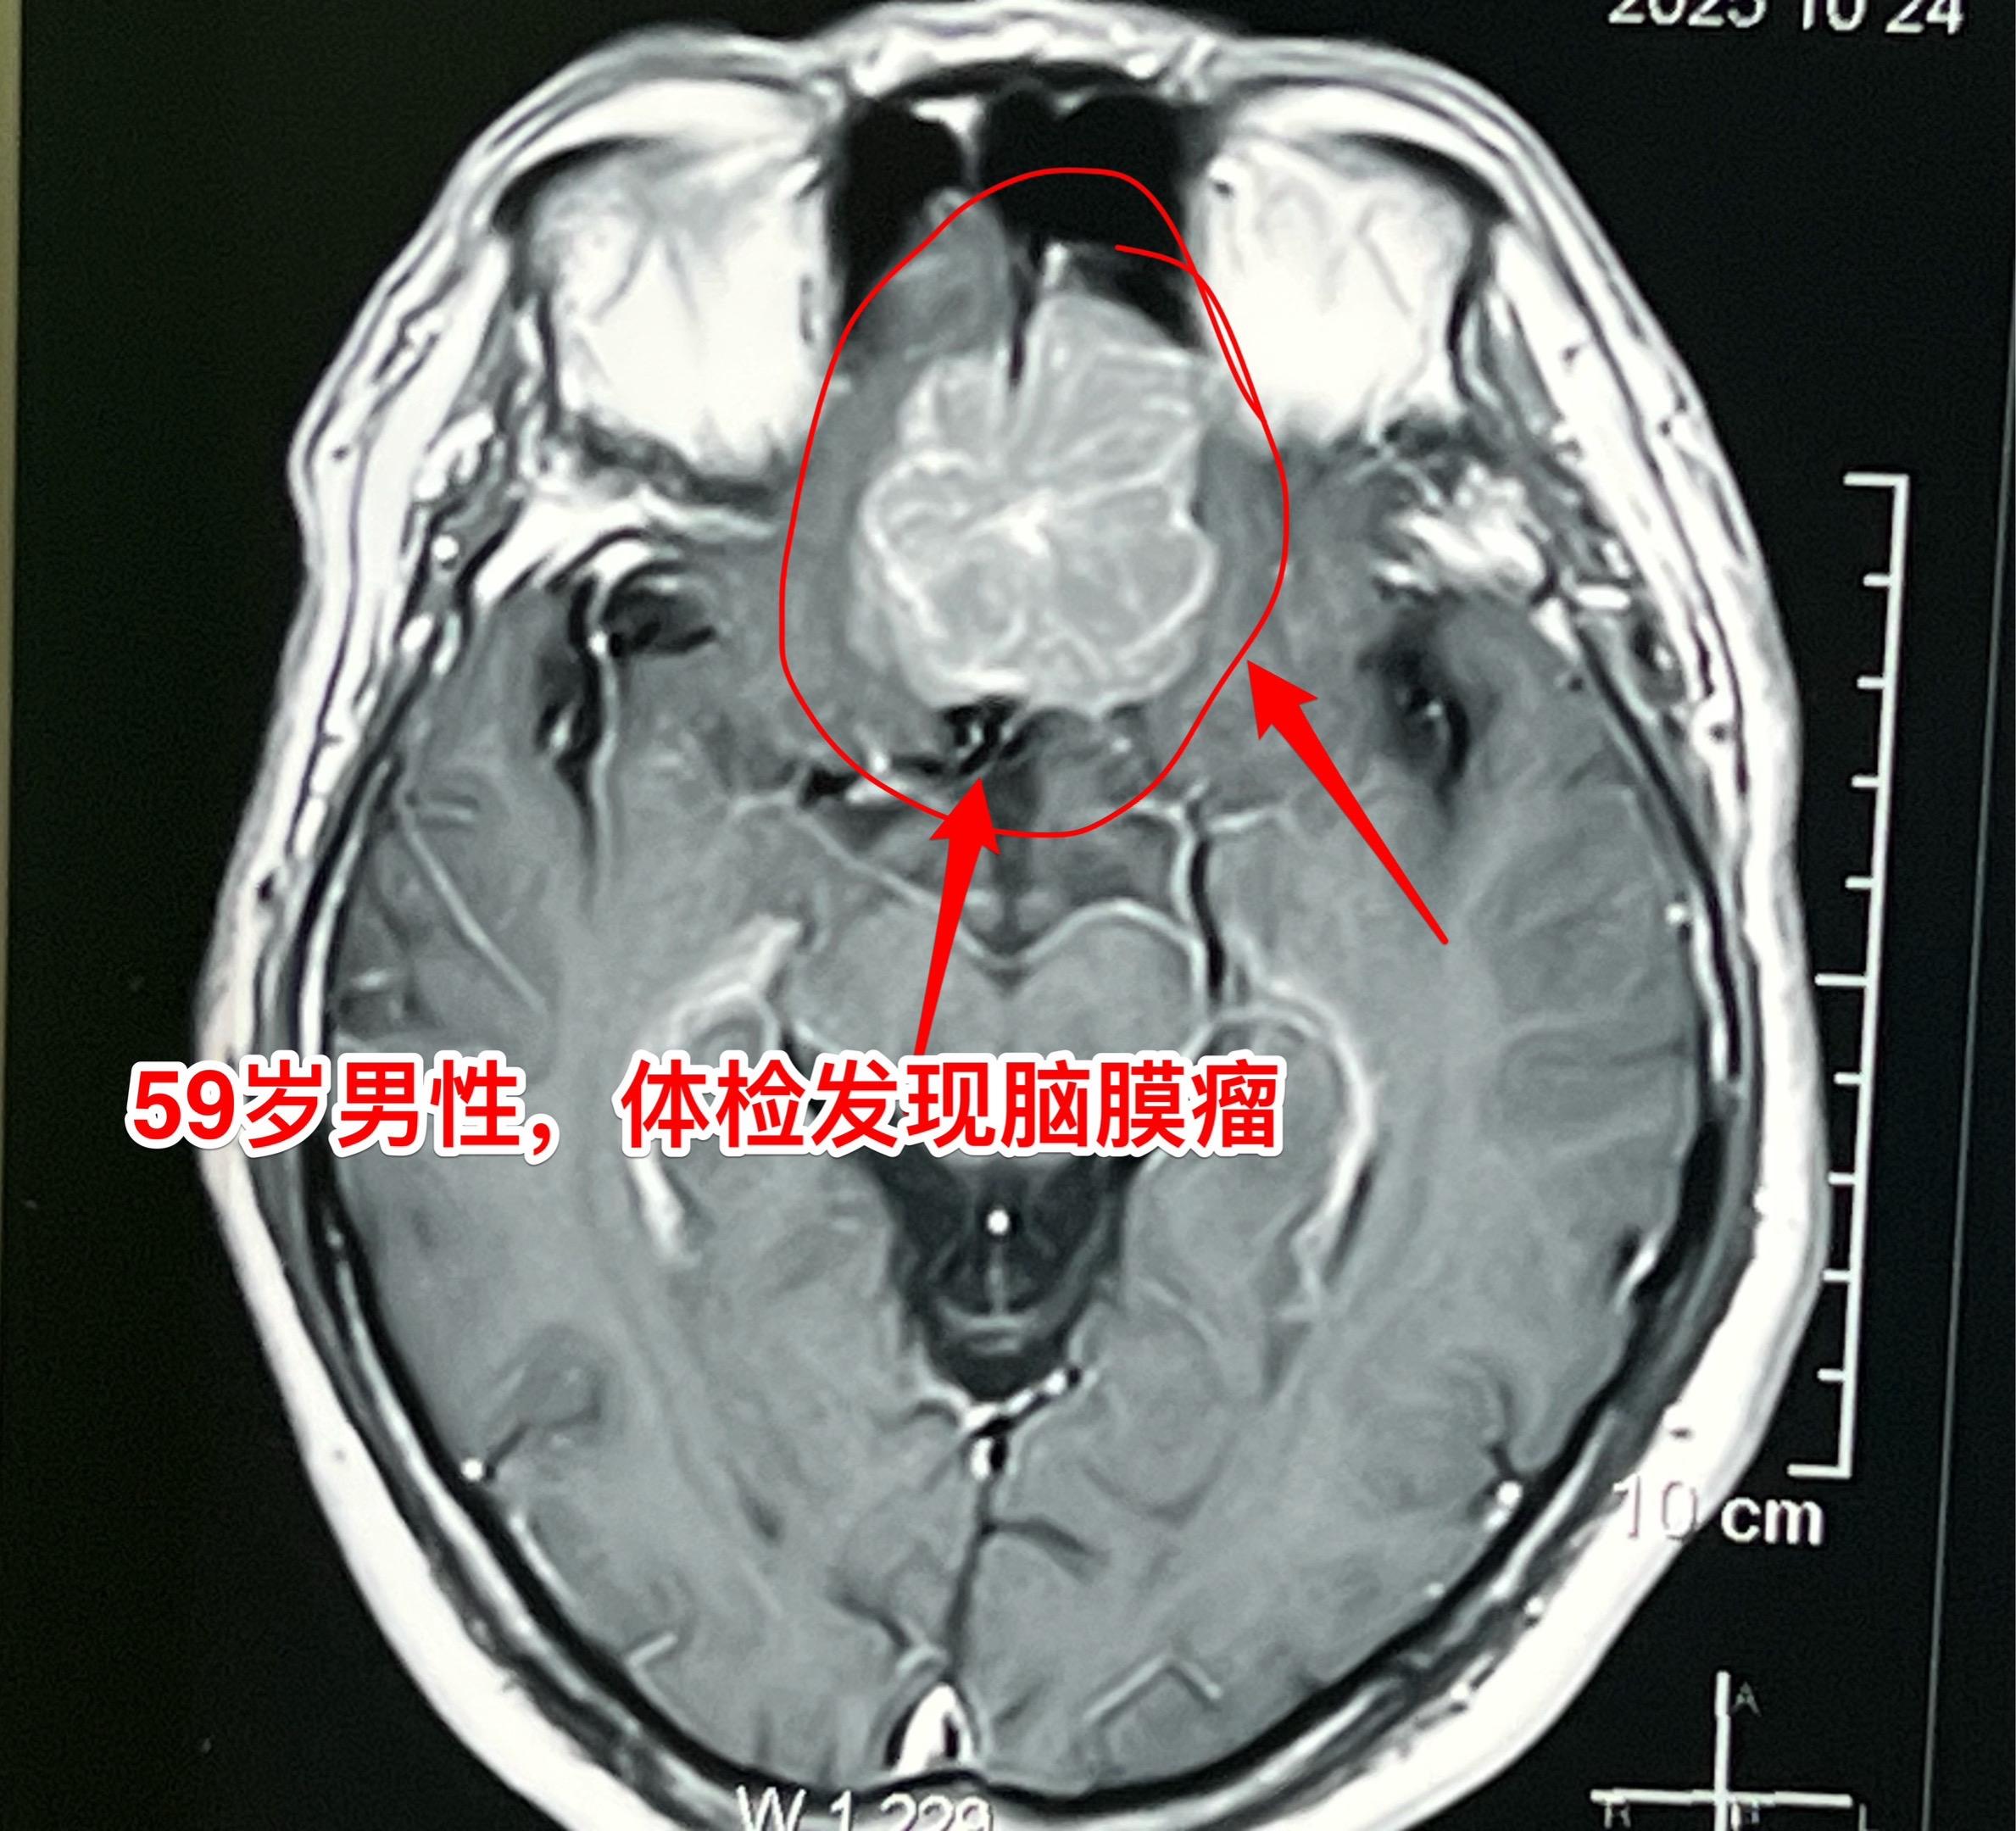

颅底脑膜瘤,彻底切除是首选治疗。59岁男性,体检发现这个肿瘤,无头痛症状,无视力下降,怀疑是脑膜瘤。 2025年10月30日作了手术,术中证实是脑膜瘤,肿瘤有完整包膜。彻底切除,争取治愈。